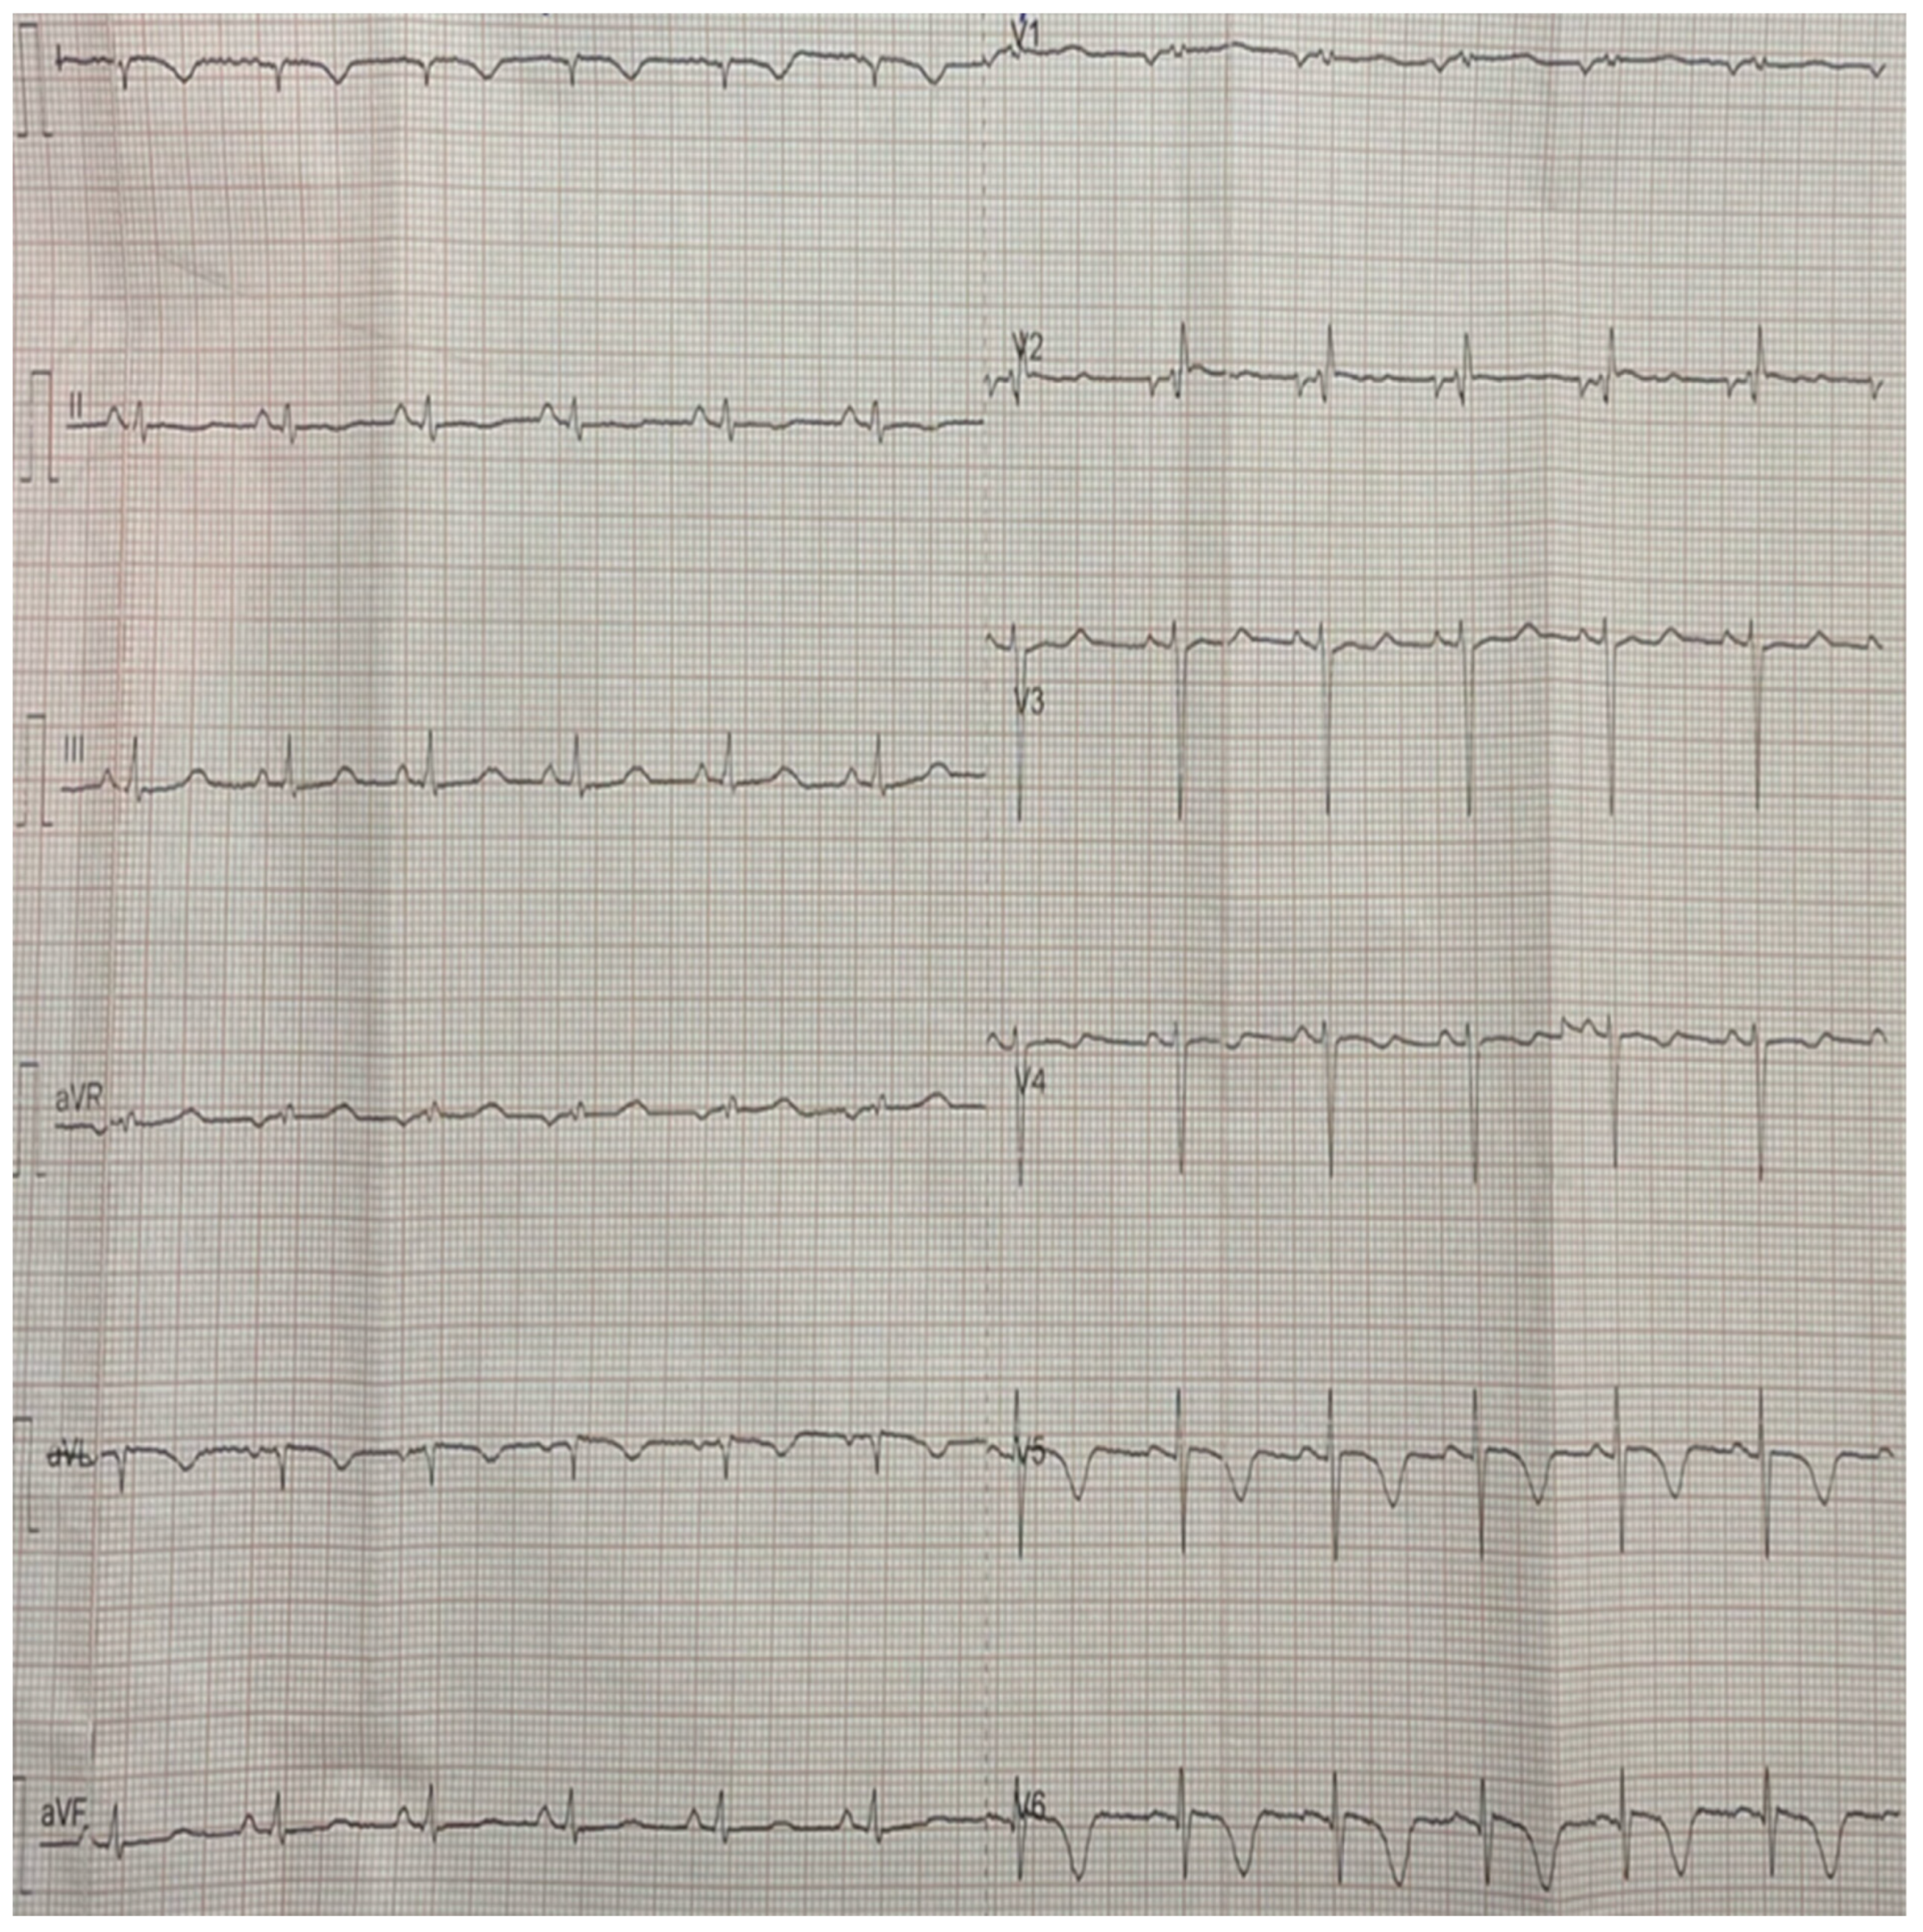

2. Case Report